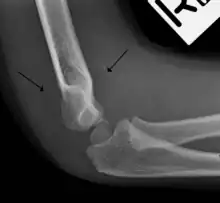

Anterior sail signs as well as posterior fat pad in a child with a supracondylar fracture.

The fat pad sign, also known as the sail sign, is a potential finding on elbow radiography which suggests a fracture of one or more bones at the elbow. It is may indicate an occult fracture that is not directly visible. Its name derives from the fact that it has the shape of a spinnaker (sail).[1] It is caused by displacement of the fat pad around the elbow joint. Both anterior and posterior fat pad signs exist, and both can be found on the same X-ray.

In children, a posterior fat pad sign suggests a condylar fracture of the humerus. In adults it suggests a radial head fracture.

The posterior fat pad is normally pressed in the olecranon fossa by the triceps tendon, and hence invisible on lateral radiograph of the elbow.[3] When there is a fracture of the distal humerus, or other pathology involving the elbow joint, inflammation develops around the synovial membrane forcing the fat pad out of its normal physiologic resting place. This is visible as the "posterior fat pad sign" and is often the only visible marker of a fracture, particularly in the pediatrics population.